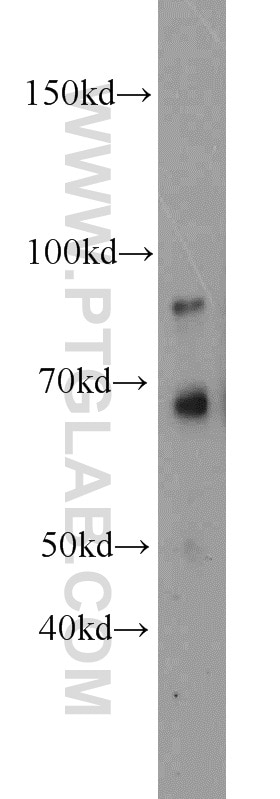

| Positive WB detected in | rat kidney tissue |

| Calculated Molecular Weight | 383 aa, 42 kDa |

| Observed Molecular Weight | 42 kDa |

NPHS2 (also known as Podocin) is a membrane protein located on the podocyte foot process and is the critical component of the glomerular filtration barrier. Mutations of NPHS2 cause recessive steroidresistant nephrotic syndrome. Two isoforms of NPHS2 exist with molecular weights of 42 kDa and 35 kDa, respectively. (PMID: 21499232)